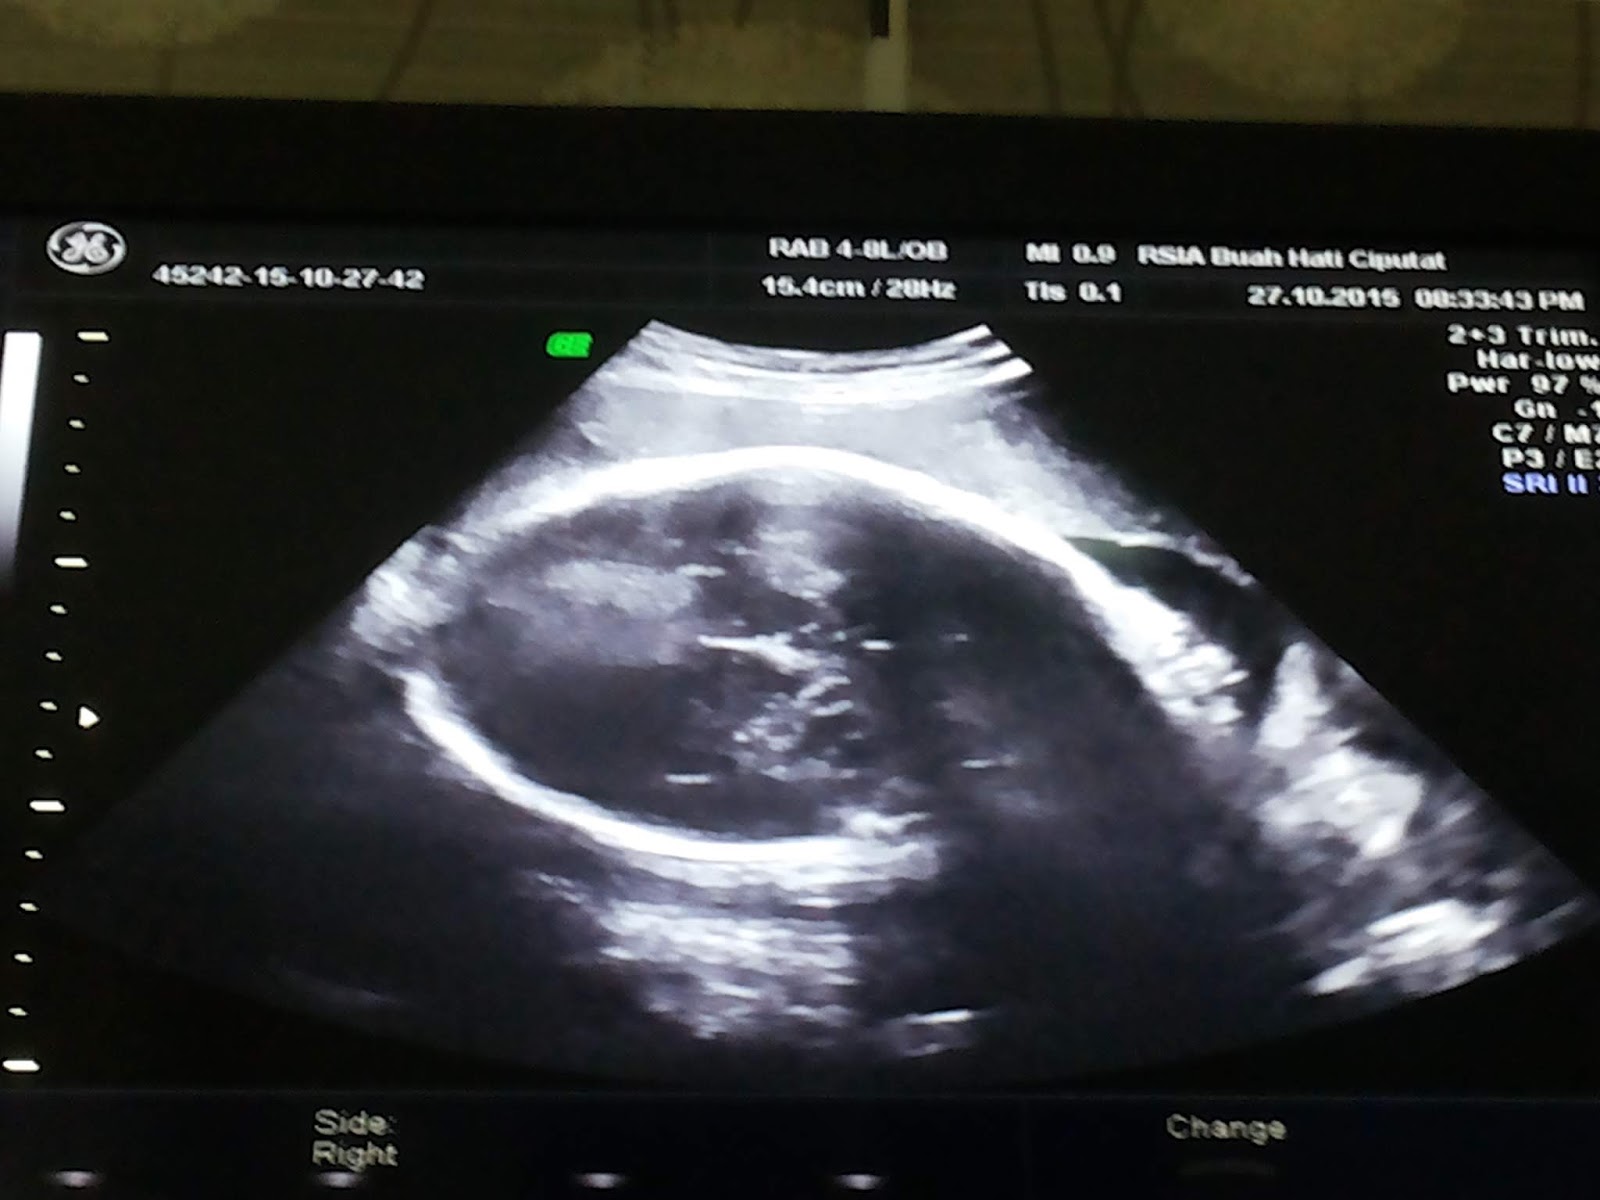

Ikut senam seminggu sekali lumayan bisa buat aku gak terlalu sesak, badan juga jadi lebih enak. Tapi ada masalah lain yang juga gak kalah heboh yaitu udah mulai susah cari posisi tidur yang nyaman. Selain ukuran perut yang semakin besar, janinnya di dalam perut juga udah mulai kesempitan. Kita saling berbagi kesulitan deh pokoknya. Hehehe. Hasil kontrol minggu ini BB ku sudah nik lagi 2 kg jadi 59 kg dan berat janinnya naik 900 gram jadi 2,4 kg. Lumayan drastis ya, secara malem udah mulai gak bisa diem si penghuni perut minta diisi makanan. Sedia biskuit, roti, susu dan air putih di kamar karena males keluar2 takut bangunin orang rumah yang lain. HB masih di 10/70 dan dijadwalkan mulai pertemuan rutin menjadi 2 minggu sekali. Wah makin sering liat kamu nak jadi gak kangen tiap bulan. Untuk posisi janin sudah menghadap ke bawah hanya belum terlalu turun. Kami berharap bisa melahirkan secara normal.

Di pertemuan kali ini ada 2 hal yang harus kami terima. Berita baik dan kurang baik. Berita baiknya, BB ibu naik 1 kg menjadi 60 kg dan BB janin naik 500 gram menjadi 2,8 kg dan HB tetap rendah di 90/60. Mungkin sedikit lelah karena beban tubuh semakin berat dan besar. Tidak ada keluhan lain selain pinggang yang semakin sering sakit, kesulitan tidur, mulai mudah merasa gerah, kram kaki hampir setiap malam, dan keluhan2 umum yang dirasakan semua ibu hamil di usia kehamilan ini. Tapi ada 1 berita buruk yang disampaikan dokter kepada kami berdua saat itu.

Posisi janin kami kembali ke atas alias sungsang. Walaupun dokternya pro normal, namun beliau tetap memberikan informasi ada kemungkinan terburuk yaitu melahirkan dengan operasi. Tapi, beliau juga tetap berharap bisa berubah posisinya sampai mendekati waktu melahirkan nanti. Dokter menyarankan untuk melakukan beberapa treatment yang biasa dilakukan para ibu yang memiliki kehamilan sungsang. Yaitu, perbanyak posisi sujud dan komunikasi dengan janin agar mau memutar. Kamipun mendengarkan saran beliau dan mempraktekkannya setiap hari sampai di pertemuan berikutnya.